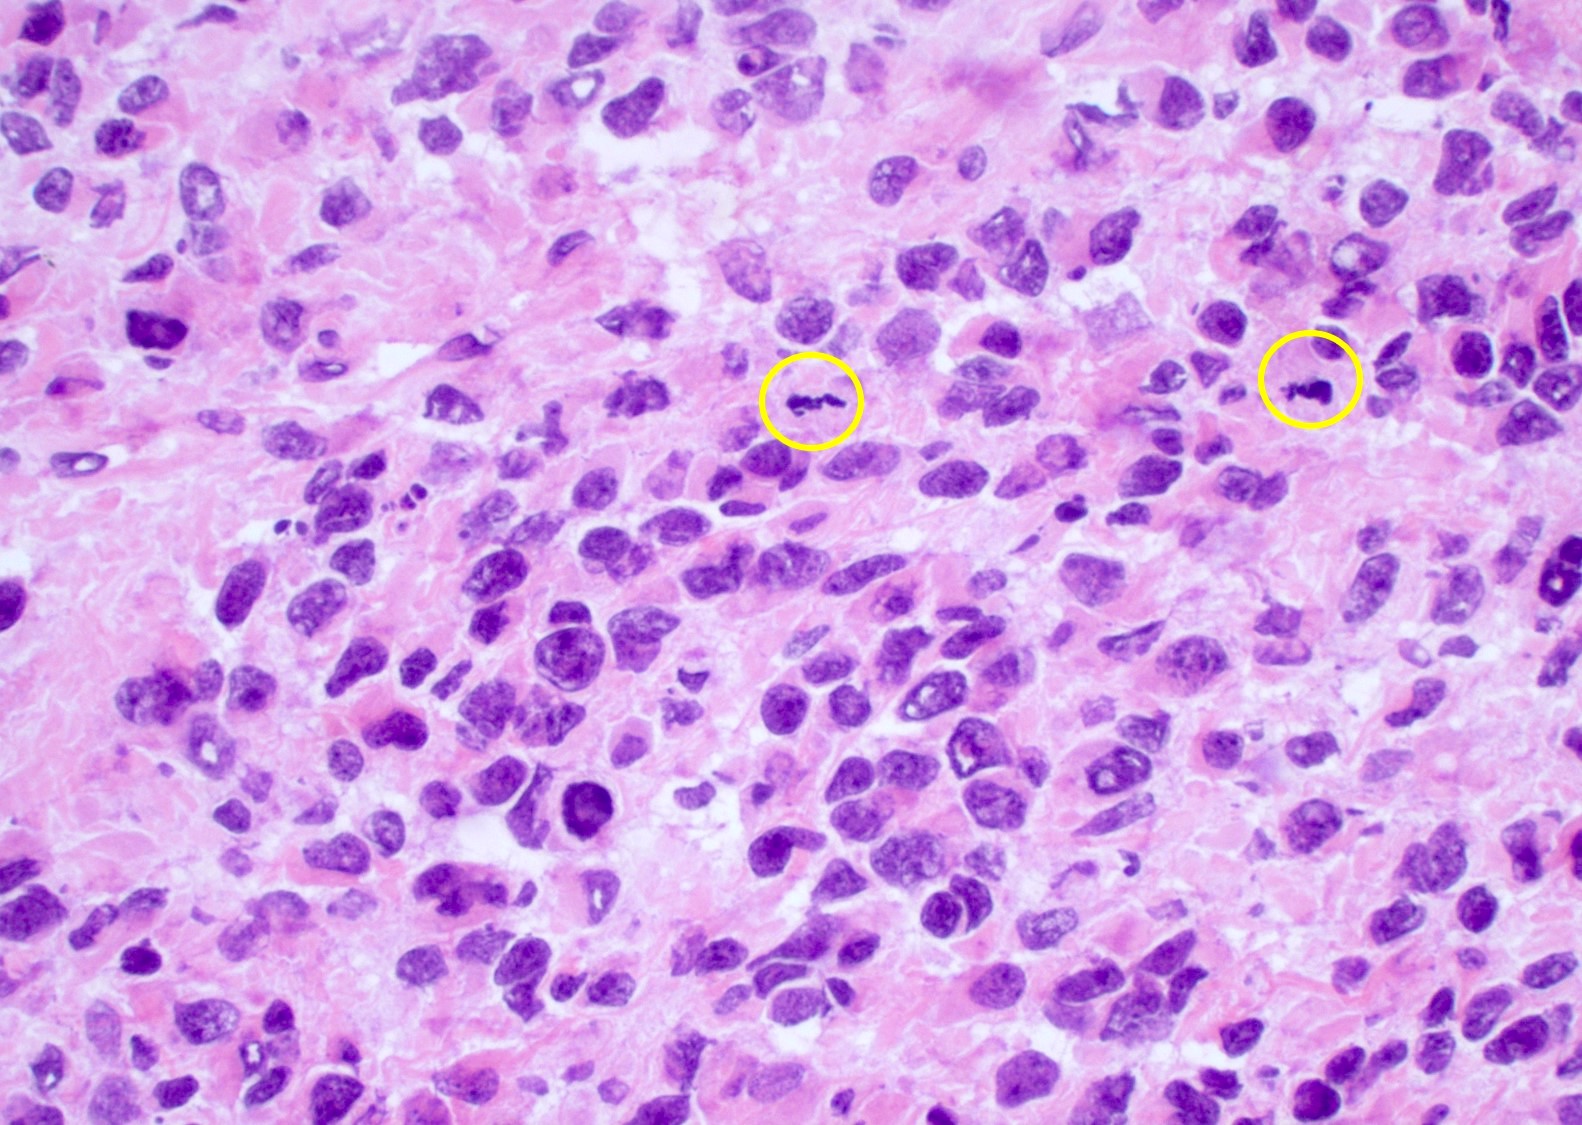

Intraoperative frozen / smear cytology images

Microscopic (histologic) description

- Infiltrating, hypercellular astrocytic neoplasm often with hyperchromatic, elongated nuclei and irregular nuclear membranes

- Typically mitotically active, though not required if molecular criteria are met

- Microvascular proliferation or necrosis is required for a histologic diagnosis of GBM

- Microvascular proliferation: multilayered, small caliber vessels with glomeruloid appearance (J Neuropathol Exp Neurol 1992;51:488)

- Necrosis: can be geographic or pseudopalisading with neoplastic cells surrounding central necrosis

- Greater association of thrombosis and necrosis in IDH wild type GBM than in IDH mutant grade 4 astrocytomas (Acta Neuropathol 2016;132:917)

- Variable cell morphology: undifferentiated / primitive neuronal cells, astrocytic, gemistocytic, oligodendroglial-like, small cell, lipidized, granular, epithelioid, giant cells, mesenchymal metaplasia and epithelial metaplasia

- Primitive neuronal cells (embryonal): markedly increased cellularity composed of cells with high N/C ratio, brisk mitotic activity with apoptotic bodies, nuclear molding, sometimes with neuroblastic rosettes

- Typically has conventional infiltrating astrocytic component, which is morphologically distinct

- Loss of glial markers, expression of neuronal markers (synaptophysin)

- Higher risk of CSF dissemination but similar survivals as classic GBM

- Associated with MYC amplifications

- Astrocytic: fibrillary, elongated processes

- Gemistocytic: abundant eosinophilic cytoplasm with eccentric nuclei

- Oligodendroglial-like: cells with small, round nuclei with perinuclear clearing in a vascular background

- Can be associated with FGFR3::TACC3 fusion positive GBM (Brain Pathol 2018;28:674)

- Small cell change: monomorphic cells with small, round or angulated, hyperchromatic nuclei and brisk mitotic activity

- Associated with EGFR amplification (Clin Neuropathol 2005;24:163, J Neuropathol Exp Neurol 2001;60:1099)

Microscopic (histologic) images

Contributed by Bharat Ramlal, M.D. and Meaghan Morris, M.D., Ph.D.

Cytology description

- Intraoperative smears may show marked cellularity, with moderate to markedly pleomorphic astrocytic / gemistocytic cells with fine fibrillar glial processes (Diagn Cytopathol 1986;2:312)

- May show necrosis

- Mitotic figures can be observed